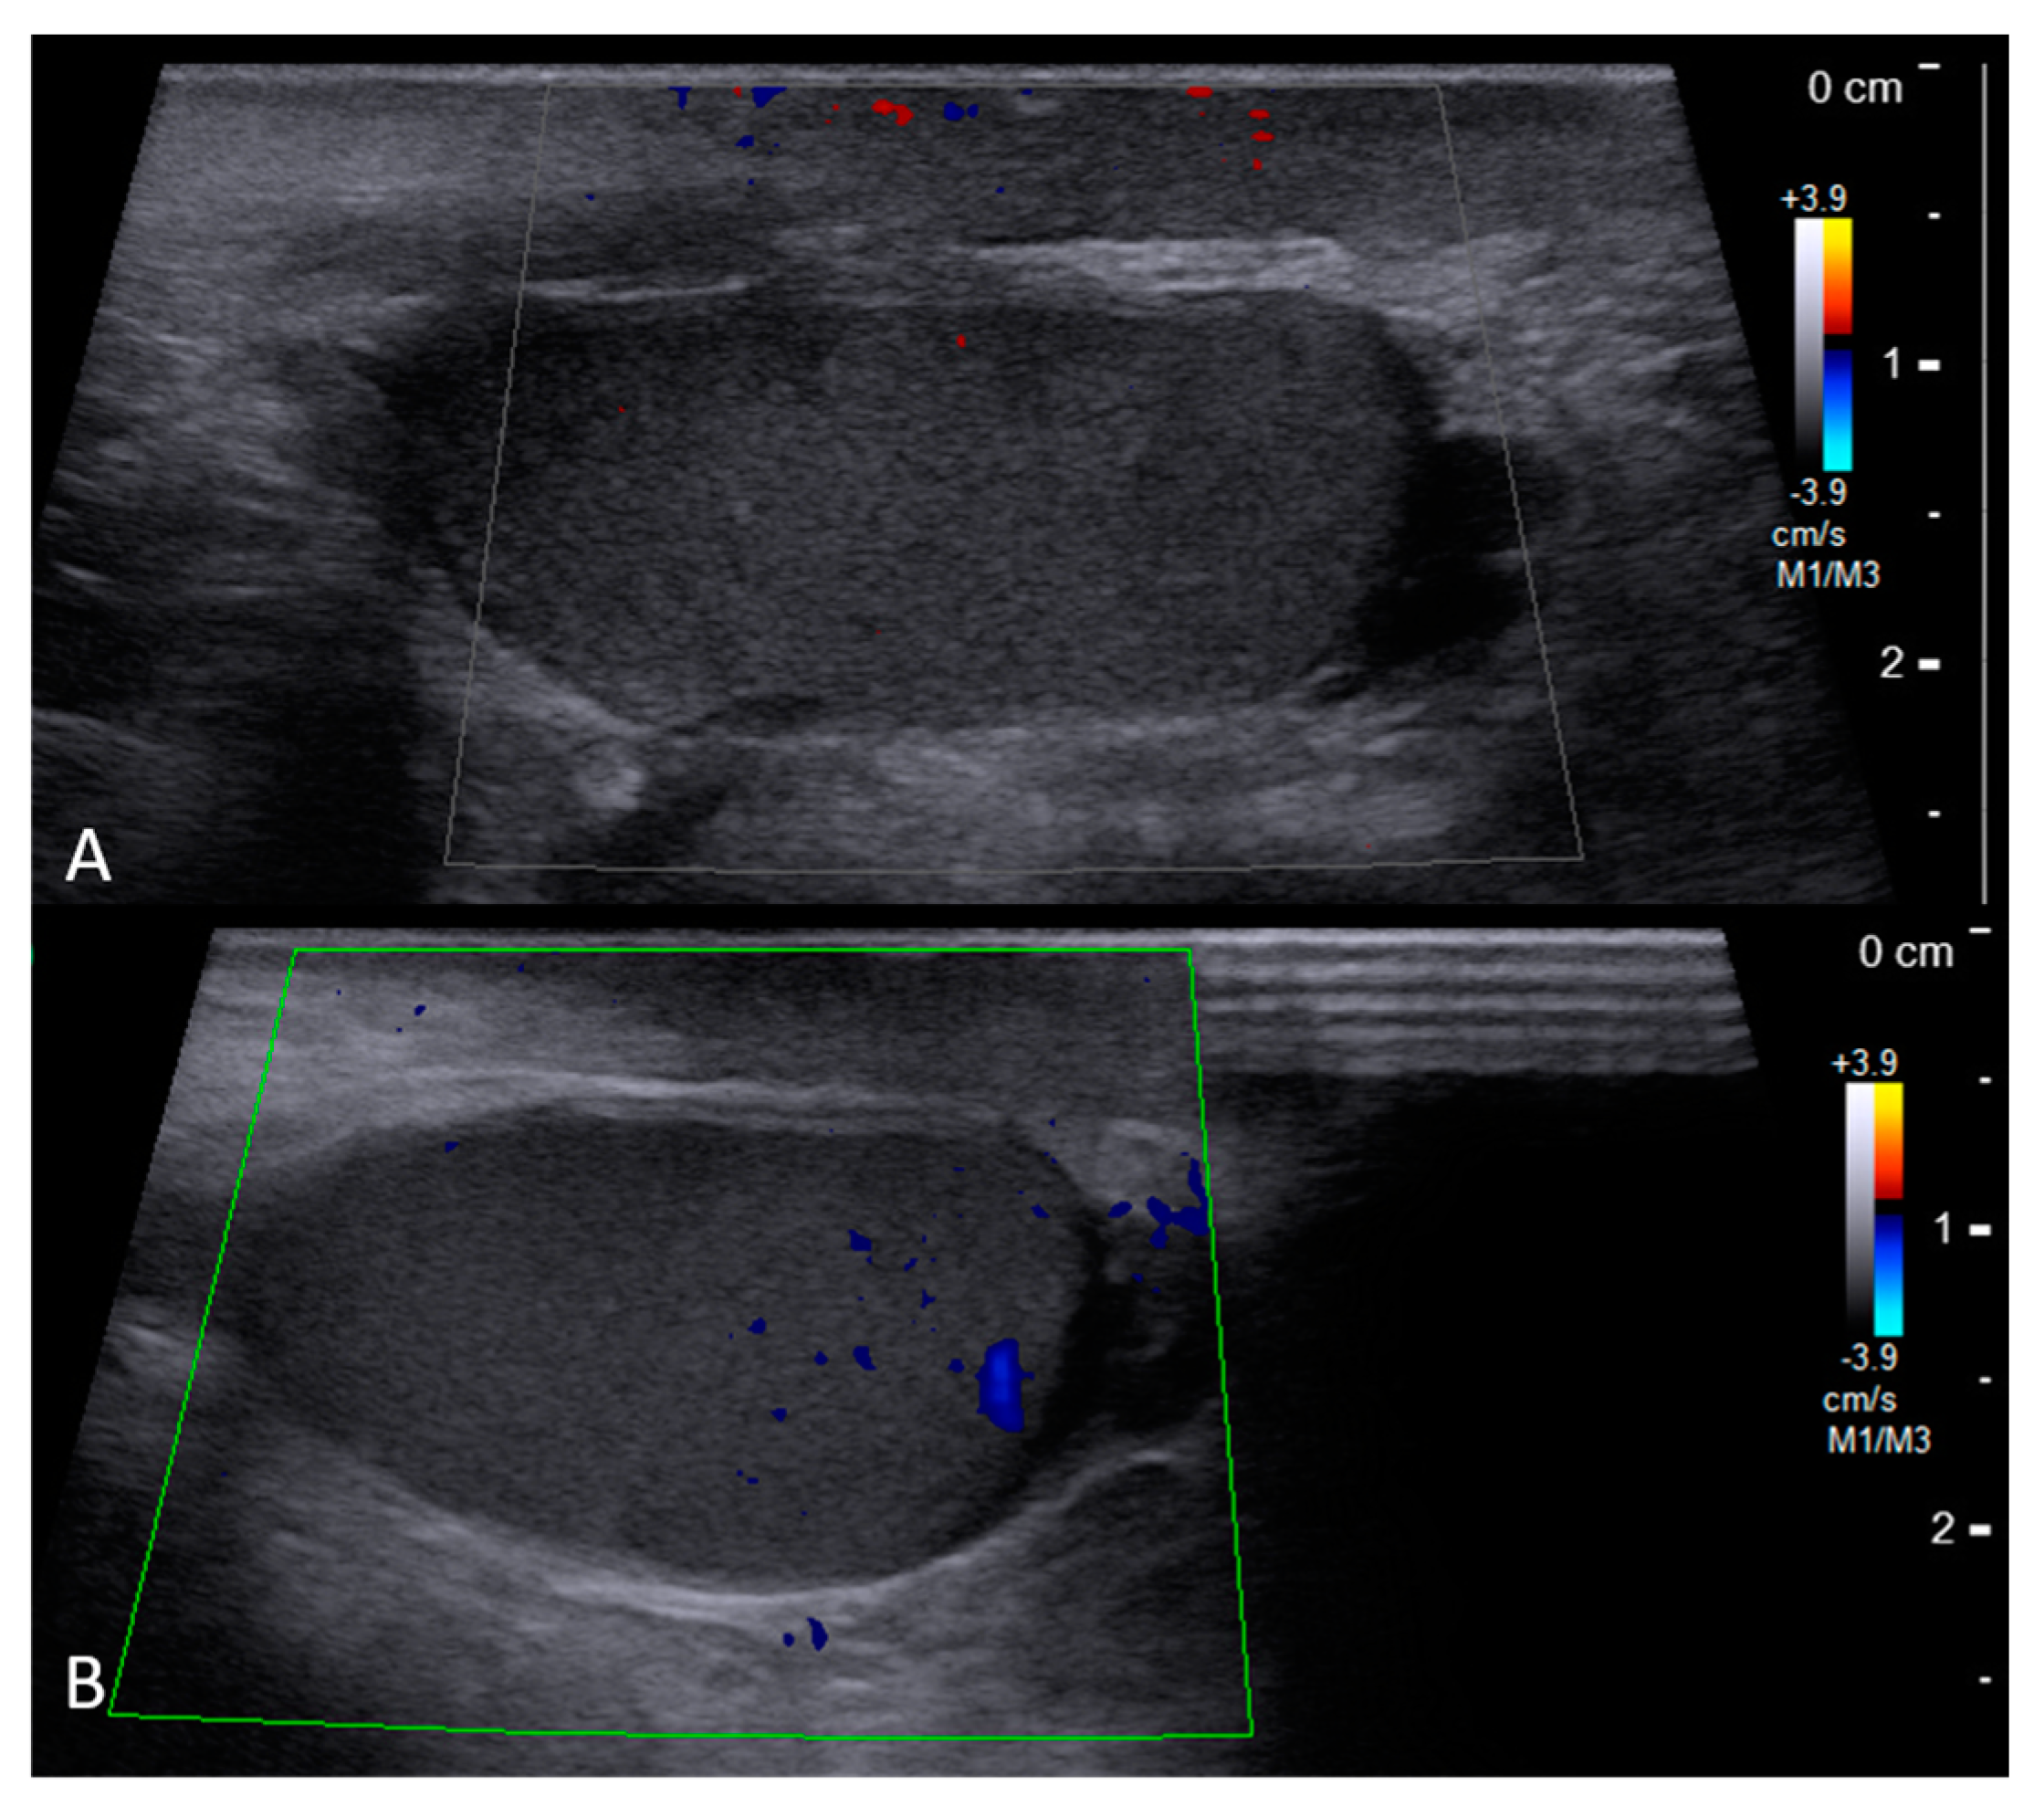

2. Case Report